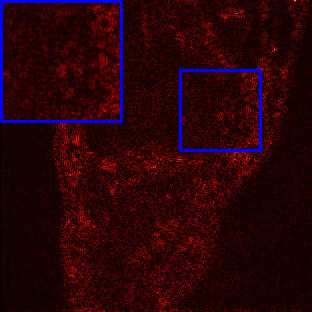

Limited by imaging systems, the reconstruction of Magnetic Resonance Imaging (MRI) images from partial measurement is essential to medical imaging research. Benefiting from the diverse and complementary information of multi-contrast MR images in different imaging modalities, multi-contrast Super-Resolution (SR) reconstruction is promising to yield SR images with higher quality. In the medical scenario, to fully visualize the lesion, radiologists are accustomed to zooming the MR images at arbitrary scales rather than using a fixed scale, as used by most MRI SR methods. In addition, existing multi-contrast MRI SR methods often require a fixed resolution for the reference image, which makes acquiring reference images difficult and imposes limitations on arbitrary scale SR tasks. To address these issues, we proposed an implicit neural representations based dual-arbitrary multi-contrast MRI super-resolution method, called Dual-ArbNet. First, we decouple the resolution of the target and reference images by a feature encoder, enabling the network to input target and reference images at arbitrary scales. Then, an implicit fusion decoder fuses the multi-contrast features and uses an Implicit Decoding Function~(IDF) to obtain the final MRI SR results. Furthermore, we introduce a curriculum learning strategy to train our network, which improves the generalization and performance of our Dual-ArbNet. Extensive experiments in two public MRI datasets demonstrate that our method outperforms state-of-the-art approaches under different scale factors and has great potential in clinical practice.